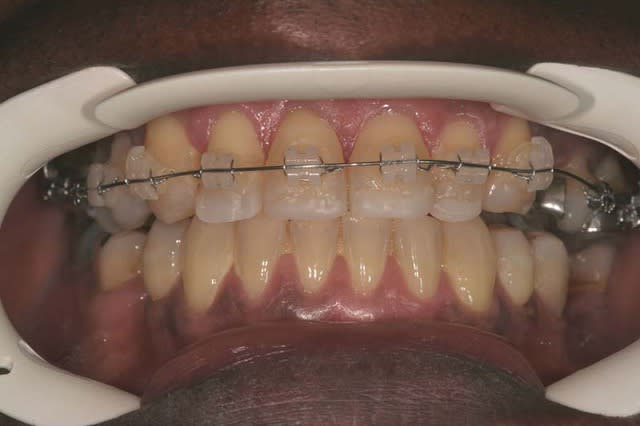

DEPART

le patient peut se mettre en bout à bout incisif

Pose d’un Q.H. à forces asymétriques

associé a un arc Sup. 0.014 thermique et a une gouttière de surélévation